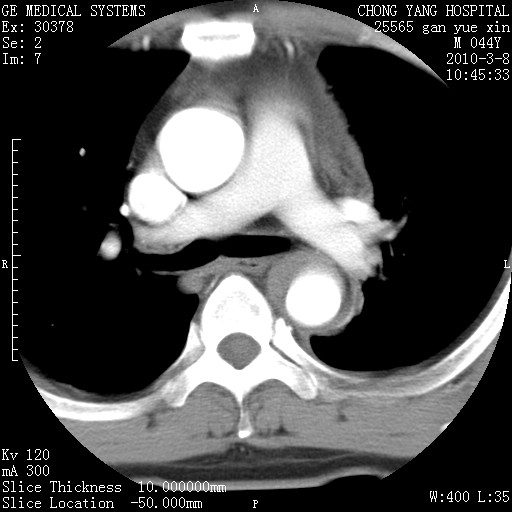

标题: CT24940:主动脉增强,典型病例。 [打印本页]

标题: CT24940:主动脉增强,典型病例。

夹层动脉瘤。

动脉夹层

夹层动脉瘤,典型

主动脉夹层。

动脉夹层的分型:

⒈debakey分型:根据主动脉夹层累及部位,分为三型:ⅰ型:原发破口位于升主动脉或主动脉弓部,夹层累及升主动脉、主动脉弓部、胸主动脉、腹主动脉大部或全部,少数可累及髂动脉。ⅱ型:原发破口位于升主动脉,夹层累及升主动脉,少数可累及部分主动脉弓。ⅲ型:原发破口位于左锁骨下动脉开口远端,根据夹层累及范围又分为ⅲa,ⅲb。ⅲa型:夹层累及胸主动脉。ⅲb型:夹层累及升主动脉、腹主动脉大部或全部。少数可累及髂动脉。

⒉stanford分型:a型:夹层累及升主动脉,无论远端范围如何。b型:夹层累及左锁骨下动脉开口以远的降主动脉。

夹层动脉瘤,少量胸水

夹层动脉瘤;左侧少量胸腔积液。

典型主动脉夹层。